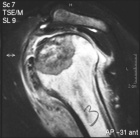

M.S. - 18 year old male with left shoulder pain

Zoom image: Radiological image Radiological image.